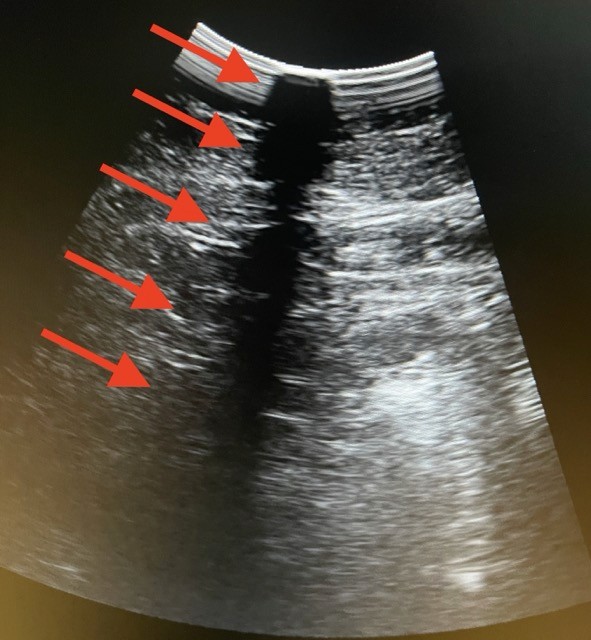

Reparación de transductor

Recupera la funcionalidad de su ultrasonido con procesos certificados, refacciones OEM y reportes técnicos claros, garantizando continuidad clínica, mayor vida útil y diagnósticos confiables.